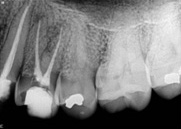

antes depois